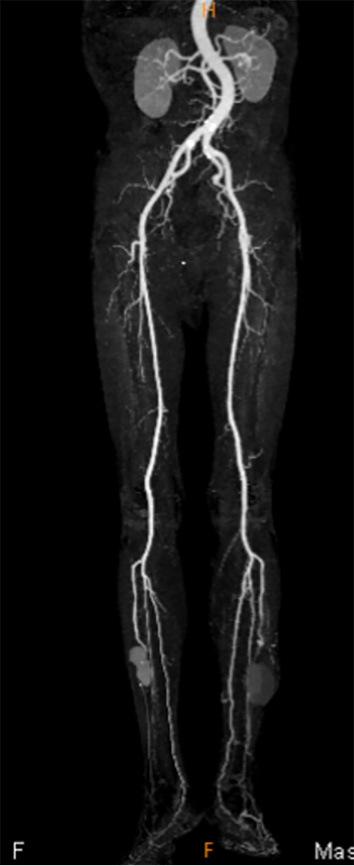

Giant Bilateral Anterior Tibial Pseudoaneurysms.

https://cdn.ncbi.nlm.nih.gov/pmc/blobs/0bef/9556228/679a6861cf98/1349-7235-61-2819-g001.jpg